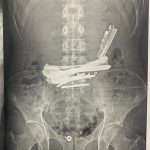

وأوضح الدكتور أحمد كمال المدير التنفيذى للمستشفيات الجامعية، أن المريض وصل إلى قسم الطوارئ وهو يعاني من أعراض خطيرة، وبعد إجراء الاشعات اللازمة تم اكتشاف وجود معادن حادة مثل ولاعات ومقصات صغيرة داخل الجهاز الهضمي، مما شكّل خطرًا كبيرًا على حياته، الأمر الذي استدعى تدخلاً جراحيًا عاجلاً لتجنب حدوث مضاعفات قد تؤدي إلى ثقب الأمعاء أو إنسداد الجهاز الهضمى.

من جانبه أوضح الدكتور علاء السيوطى رئيس قسم الجراحة العامة وجراحات الأورام والمناظير، انه تم التعامل مع الحالة جراحيًا بمنتهى الدقة لإستخراج الأجسام الغريبة بنجاح، مع التأكد من سلامة الجهاز الهضمى وعدم حدوث أي مضاعفات، كما تم عرض المريض على استشارى الأمراض النفسية لوضع خطة علاجية تمنع تكرار مثل هذه الحوادث مستقبلًا، مشيرًا إلى أن المريض خرج من المستشفى بحالة جيدة بعد استكمال فترة المتابعة والعلاج.